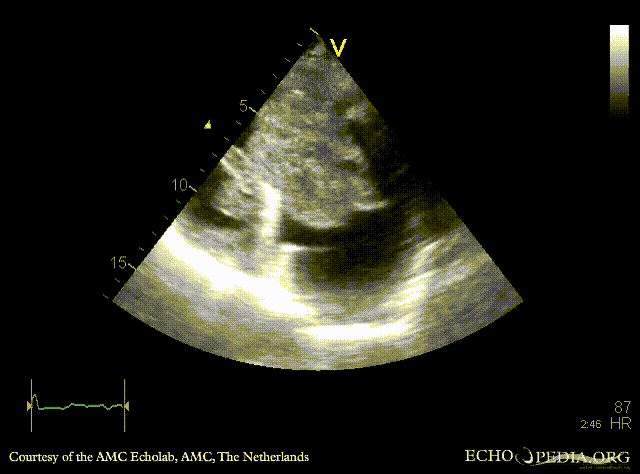

| Giant myxoma in right atrium

| Subcostal view